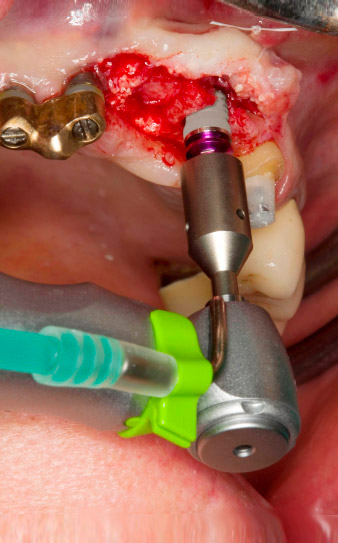

Im Rahmen der Freilegung für die Implantation an Position 23 wird vier Monate später die Implantatstabilität mit dem im Gerät integrierten W&H Osstell ISQ-Modul gemessen (Implantat-Stabilitäts-Quotient).

Dafür wird der zum Implantatsystem passende Messpfosten (SmartPeg) aufgeschraubt und die Sonde in einem Abstand von 3-5 mm von der Stirnseite des Messpfostens positioniert (Abb. 7).

Im Fallbeispiel wurde auch das optional integrierbare W&H Osstell ISQ-Modul genutzt (Abb. 7). Da die Einheilung des Implantats gedeckt erfolgte, konnte deren erfolgreicher Abschluss bestätigt werden (Implantat 22). Wenn eine Sofort- oder Frühbelastung geplant ist, lässt sich mit dem Modul – in Verbindung mit dem registrierten Drehmoment – die nötige Primärstabilität überprüfen. Alle Daten können sitzungs- und implantatbezogen auf USB gespeichert werden. Damit sind neben den klinischen auch die forensischen Anforderungen in vorbildlicher Weise erfüllt.